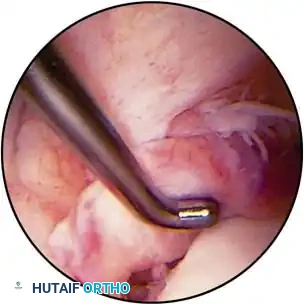

Posteromedial Compartment The posteromedial compartment can be viewed either through a posteromedial portal, as described previously, or with a 30or 70-degree oblique arthroscope passed through the intercondylar notch from the anterolateral or transpatellar tendon portal. Use of a 30-degree oblique arthroscope is optimal if viewing is done through a posteromedial portal. Structures examined from these approaches are the peripheral attachment of the posterior horn of the medial meniscus, the posterior meniscus synovial refl ection, the distal half of the posterior cruciate ligament, the posterior femoral condyle, and the confi nes of the posteromedial capsular and synovial compartment, to which free loose bodies and meniscal fragments tend to gravitate. When this compartment is viewed through an anterior portal through the intercondylar notch, the arthroscope passes between the posterior cruciate ligament and the medial femoral condyle (see Fig. 48-7D). This passage usually requires a slight degree of knee fl exion and valgus stress. When viewed through an anterior portal, the posterior cruciate ligament and posterior horn of the medial meniscus can be probed by inserting the probing instrument through a posteromedial accessory portal. If a 70-degree arthroscope is placed through the intercondylar notch, the leg can be positioned so that there is a slight hip fl exion, external rotation, and abduction and knee fl exion, to allow the posteromedial compartment to billow out. An accessory posteromedial instrumentation portal can be established under direct vision if necessary. A spinal needle can be inserted under direct vision to locate the optimal portal site accurately. Alternatively, a 30-degree arthroscope can be introduced through a posteromedial portal for viewing the posteromedial compartment (see Fig. 48-7E). With the knee placed in a fl exed, abducted, externally rotated position, the posteromedial compartment is maximally distended. An 18-gauge spinal needle can be used to identify the soft spot safely. The location of the portal should be about 1 cm above the posteromedial joint line and at the posteromedial margin of the femoral condyle. To protect the nearby saphenous vein, only the skin should be incised. A sheath and sharp trocar are passed through the skin and subcutaneous tissue down onto the posterior aspect of the medial femoral condyle. The sharp tip of the trocar should be used to engage the capsule, then the trocar is slid posteriorly off the condyle, and the capsule is penetrated. Without engaging a portion of the capsule with the tip of the trocar, the trocar can sometimes glance off the capsule posteriorly instead of penetrating it. Excessive pressure should not be applied against the posteromedial femoral condyle as the trocar is introduced because this could gouge the articular cartilage. Removal of the trocar from the sheath results in escape of irrigating solution when the sheath is in the proper position. The arthroscope is introduced, and after the camera has been righted, the lens should be turned anteriorly to face the posterior aspect of the medial femoral condyle. This is the landmark that orients the surgeon. When this is identifi ed, the lens can be turned inferiorly to view the meniscocapsular junction of the posterior third of the medial meniscus. In the depths of the posteromedial compartment, the posterior cruciate ligament can be seen. A probe can be inserted through the anterolateral portal and passed between the posterior cruciate ligament and the medial femoral condyle to enter the posteromedial compartment. The probe can be used to probe the posterior third of the medial meniscus and the posterior cruciate ligament.